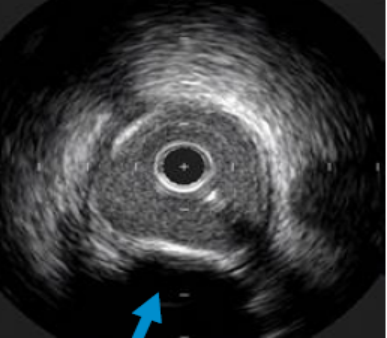

如图1所示:

1: 外膜是由胶原蛋白组成,超声反射信号强烈(显示为白色)

2: 中膜是由平滑肌细胞组成,无超声回波信号(显示为灰色)

3: 内膜致密,介于中膜和血流之间,显示为白色;

4. 管腔:血液;

5. 衰荡区:“光晕”;

6. 盲区:导管。

图1 血管在超声下的图像